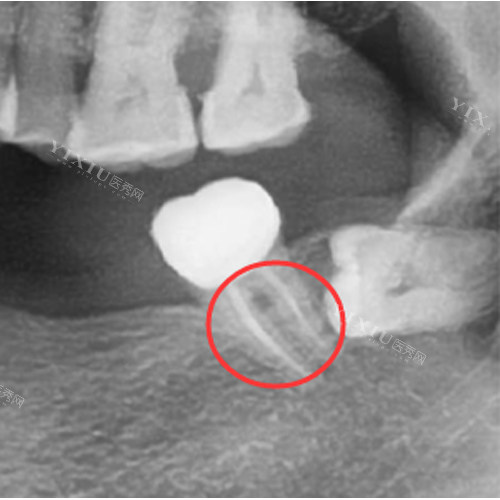

严峻的根尖周病变:如果牙髓炎没有得到及时治疗,炎症会扩散到根尖周组织,导致根尖周脓肿、囊肿等病变。当根尖周病变范围较大,经过多次根管治疗仍无法治疗好,或者牙齿已经出现严峻的松动,无法保留时,就需要拔牙。

根管治疗过程